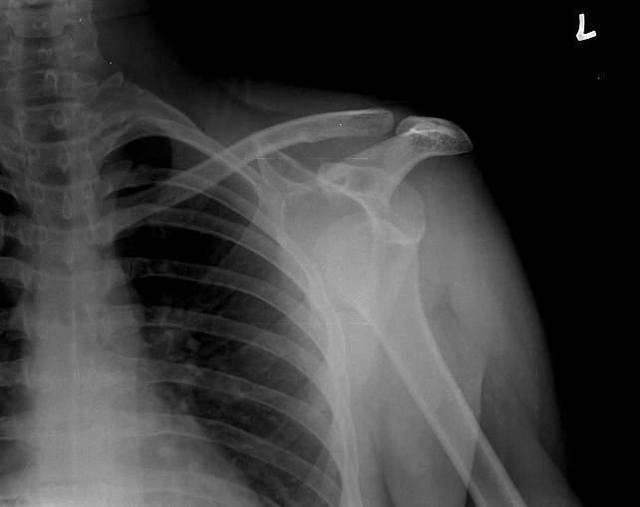

Prvotní vymknutí hlavičky kosti pažní je vždy doprovázeno rupturami (roztržením) kloubního pouzdra, defekty vazů, otokem a výraznou bolestivostí, výjimečné nejsou ani zlomeniny hlavice humeru či okrajů kloubní jamky.

K repozici v podmínkách zdravotnického zařízení se přistupuje v celkové či alespoň lokální anestezii, samozřejmě po kontrole na RTG. Následné znehybnění by nemělo být kratší než dva týdny. Zlomeniny musí být vždy řešeny operativně.

V článku jsem nepostřehl podstatnou maličkost. Při přímém úderu do ramene nebo do paže může dojít k poškození hlavice kosti pažní. Následné agresivní manévry s paží mohou způsobit poškození cév a nervů. Z posledních let mám zdokumentovány dva případy, které se navenek jevily jako obvykle vykloubené rameno. Podlitiny a následné RTG ukázaly poškození hlavice kosti pažní. Rozhodně nedoporučuji „nahazovat“ rameno u všech nárazů do paže a v okamžiku, kdy nemohu postiženého vizuálně zkontrolovat bez oblečení. Zde popisované agresivní metody repozice mohou způsobit nevratná poškození.